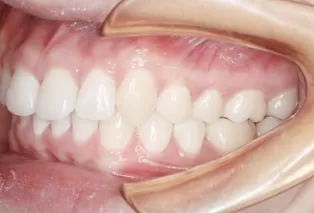

Intraoral photos after treatment